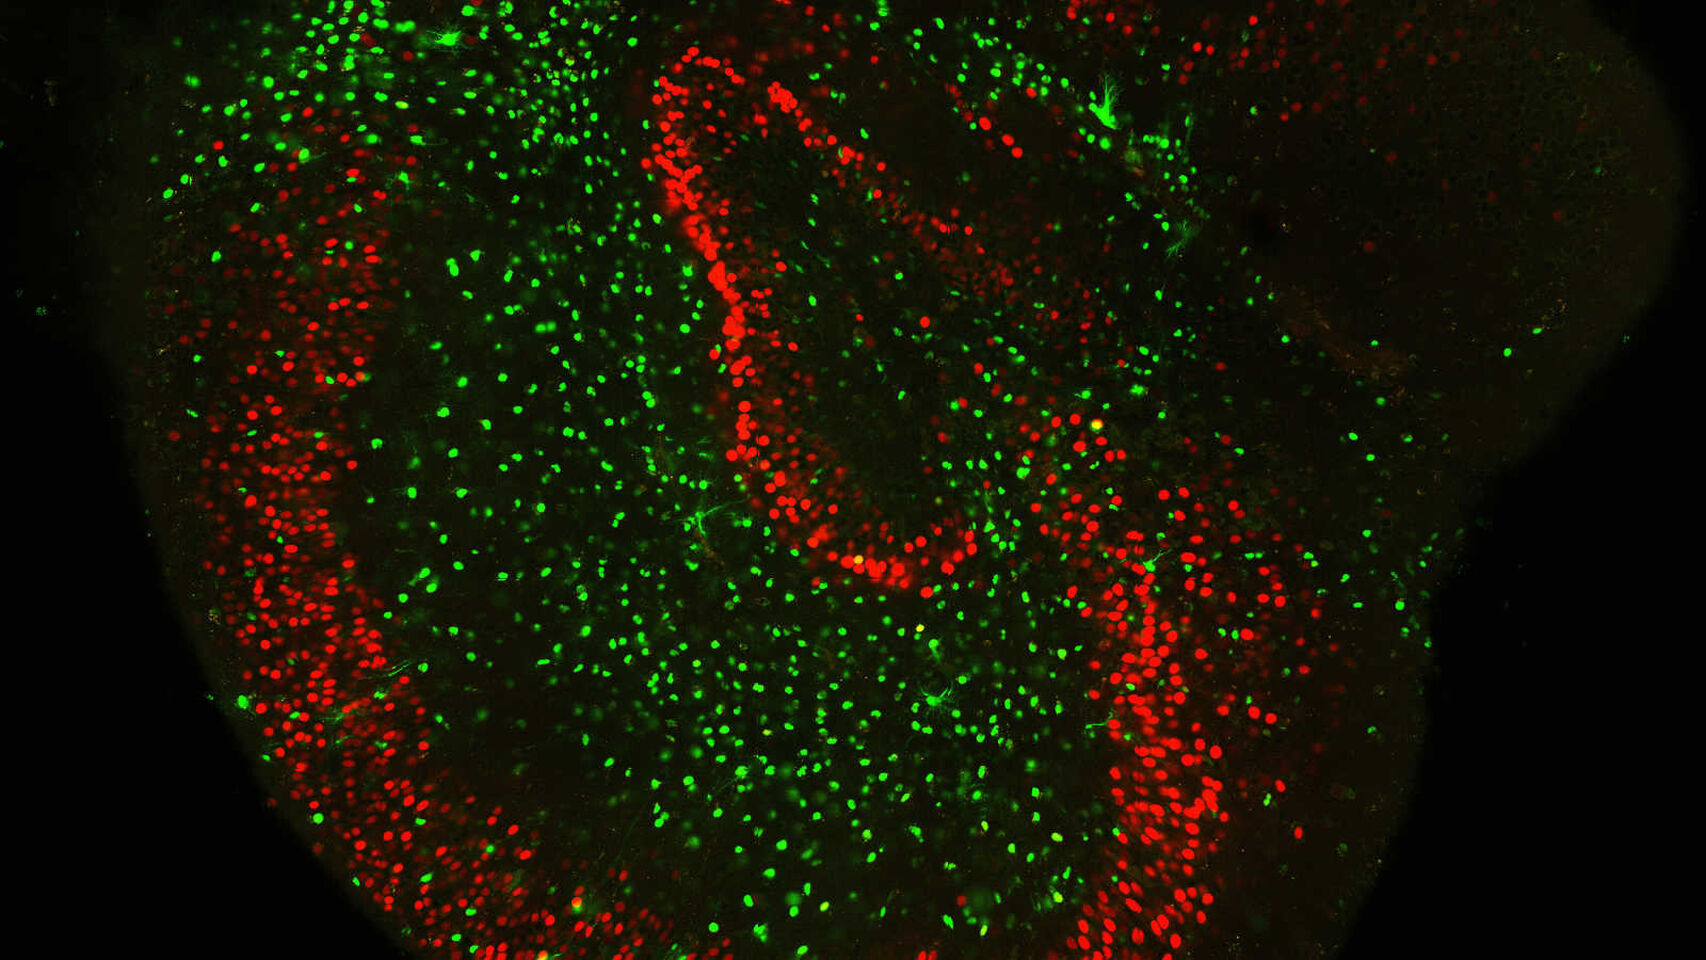

El hallazgo supone la identificación de una diana terapéutica para el alzhéimer, una patología incurable en la actualidad. El cerebro es un conjunto organizado de células que recibe, procesa, transmite y almacena información. Una de sus propiedades más interesantes es […]